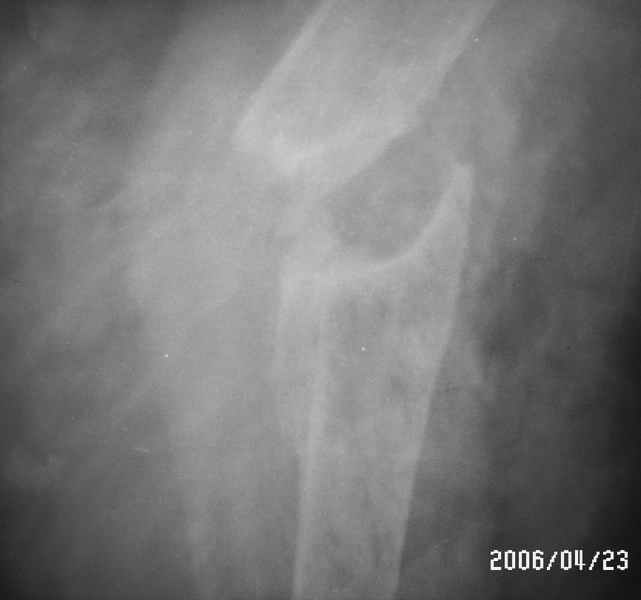

Уважаемые коллеги! Помогите в выборе тактики лечения больной Р.,56 лет, с болтающимся ложным суставом с/3 правой плечевой кости 2-х летней давности. В анамнезе - бронхиальная астма, гормонозависимая форма, ожирение III cт. Травма - автодорожная, получила закрытый многооскольчатый перелом диафиза плечевой кости со смещением (от метафиза до метафиза), в экстренном порядке нами произведен закрытый остеосинтез стержневым аппаратом, отломки удалось сопоставить анатомически. В дальнейшем больная выпала из поля зрения. Как потом выяснилось, после снятия стержневого аппарата, больная долечивалась по Илизарову специалистом из г. Кургана. Аппарат Илизарова удален из-за нагноения мягких тканей. Последние два года работая бухгалтером, фиксирует плечо ортезом. Теперь вновь обратилась к нам для ликвидации ложного сустава.